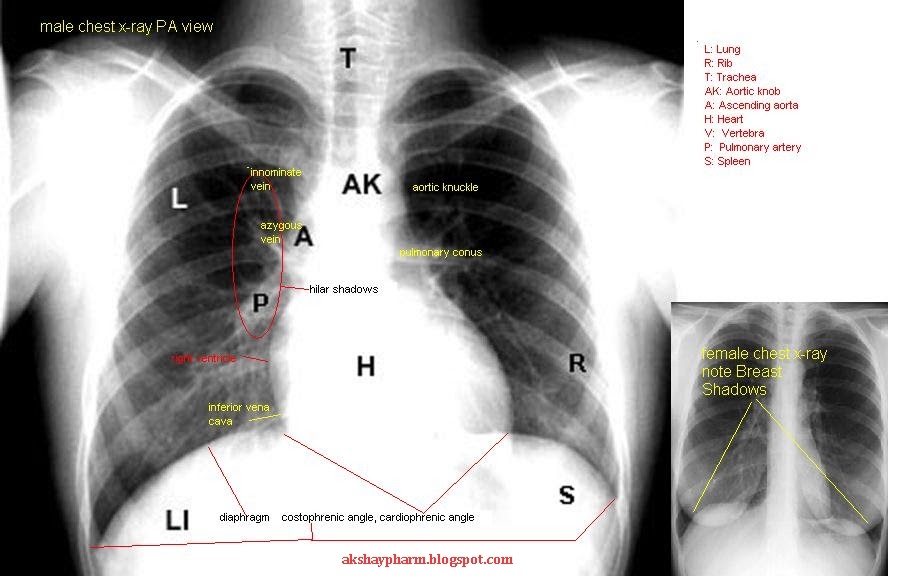

From srkiqtfwqzfwzf.blogspot.com

Anatomy Of Chest X Ray Normal Chest Xray Stock Photo Download Image What To Eat Before Chest X Ray  You'll need to remove jewelry from the waist up,. • it is ok to eat a light meal before. Since we don’t always know when we’ll need to have an x.  how should i prepare? Nhcs cardiology @ skh, sengkang general hospital. Also called a radiograph, this test gives the healthcare provider information on.  article contributed by department. What To Eat Before Chest X Ray.